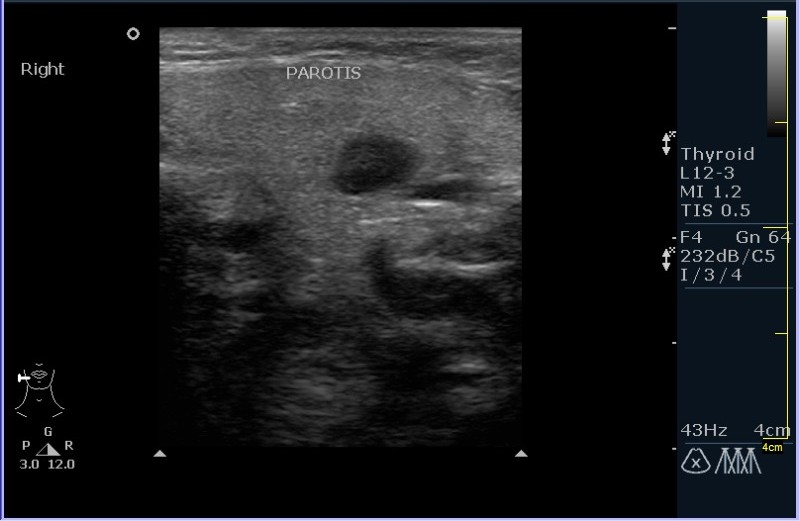

УЗИ области правой околоушной железы и угла нижней челюсти.

Девочка 8 лет, с опухлостью щеки и области правого угла нижней челюсти, резко боезненной при пальпации. В анамнезе (после наводящих вопросов :ugeek: ), визит к стоматологу около месяза назад.